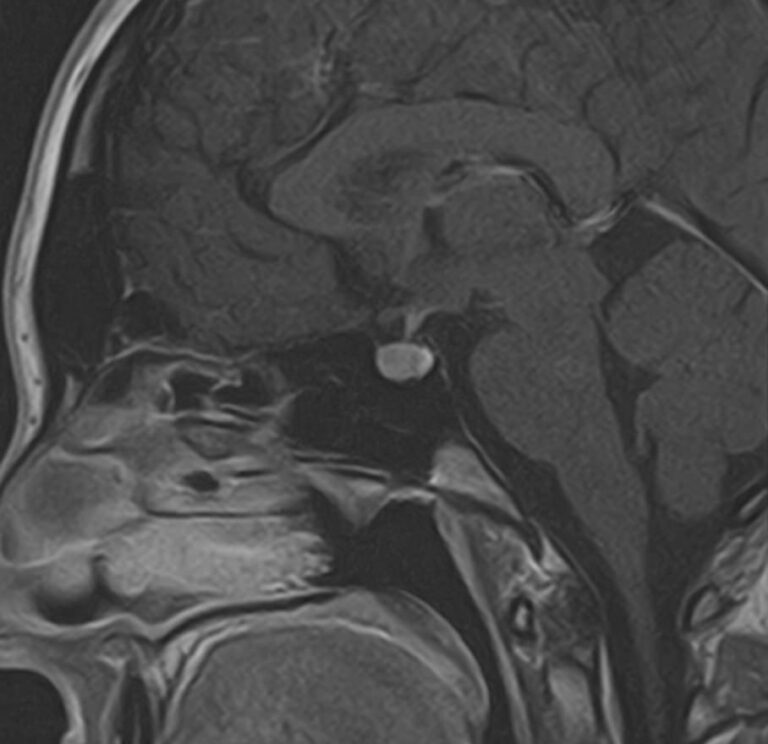

Поскольку гипофиз имеет очень маленькие размеры и расположен в глубине головы, досконально изучить его структуру можно только с помощью МРТ. Ни один другой из существующих методов визуализации не способен дать настолько четкие изображения и данные о состоянии гипофиза. Расшифровка результатов выполняется рентгенологом.

С помощью МРТ гипофиза можно создать его трехмерное изображение с высокой степенью детализации. Это позволяет обнаружить патологические изменения на самых ранних этапах, начиная от аномалий развития, сосудистых нарушений, воспалительных процессов и заканчивая опухолями разной природы.

МРТ гипофиза выполняется в нашей клинике выполняеется только с контрастным усилением, что повышает четкость получаемых изображений, а по особенностям распределения контрастного препарата в тканях можно с высокой точностью не только обнаружить доброкачественные и злокачественные опухоли, но и исследовать их локализацию, структуру, определить границы и заметить метастазы.

Чаще всего исследование проводится для диагностирования аденомы гипофиза и определения ее величины: микроаденомы (до 10 мм), макроаденомы (10—30 мм) и гигантской аденомы (более 30 мм). Также с его помощью обнаруживается неоднородностьструктуры, асимметрия границ, изменения положения воронки гипофиза и ее строения, а также деформации окружающих костных тканей.